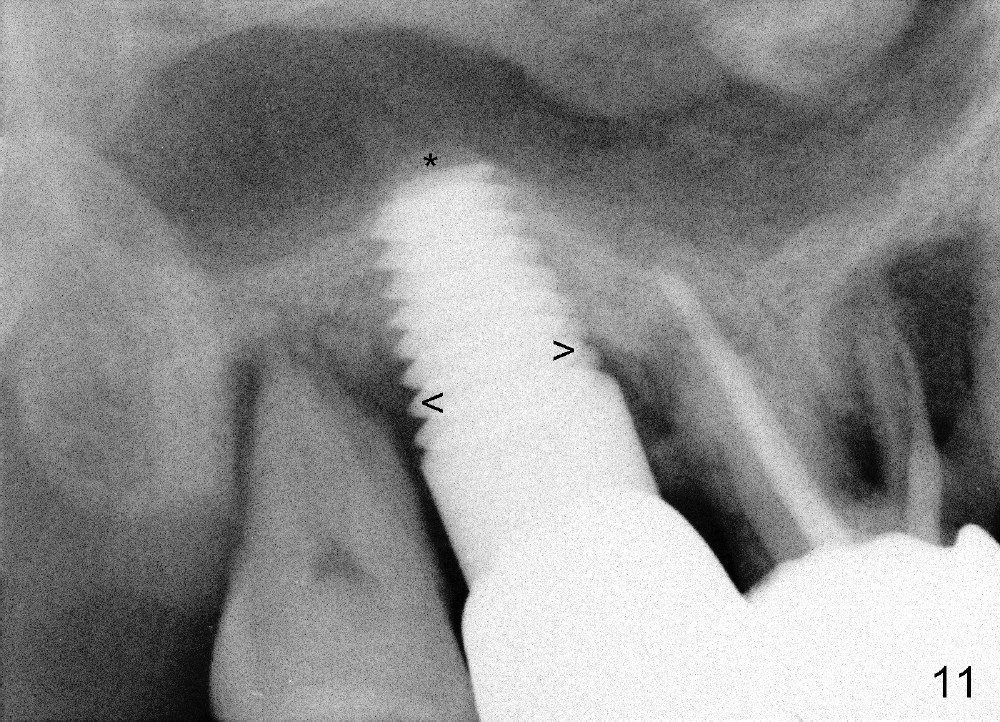

Six months post cementation, the patient returns for follow-up (Fig.11-14) with chief complaint of food impaction between the upper right last 2 teeth. It is difficult to remove. The distal 2nd thread appears not to be covered by the bone, whereas the mesial one is (compare Fig.11 arrowheads). The buccal gingiva is apparently within normal limit (Fig.12) except the distal (Fig.13 >). The distolingual gingiva recession is much more severe (Fig.14). There are deep pockets with tenderness in the abnormal sites. The tooth #1 has #2 mobility with tenderness. The patient agrees to have it extracted and restored with an implant, since the tooth #32 is functional. Bone graft will be placed in the lingual aspect of the implant at the site of #2.